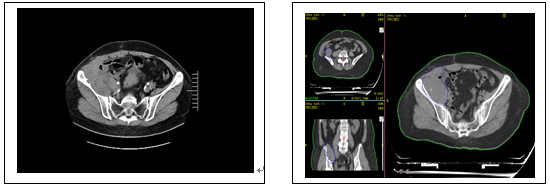

下图为放疗前病变及放疗靶区